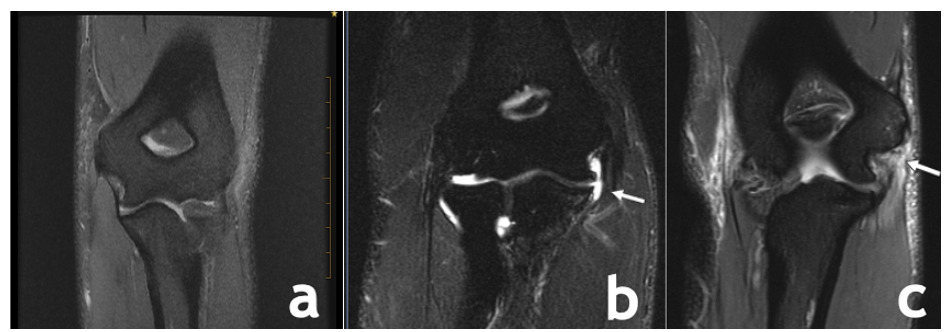

To further determine specific involvement other tests such as radiographs are used to evaluate for potential osseous involvement such as stress fractures, osteochondritis dessicans lesions, or avulsion fractures of the sublime tubercle, as well as the buildup of calcium deposits within the ligament in chronic cases of UCL injury. The usual radiographic series utilized to assess the osseous structures of the elbow are listed in Table 1. Magnetic resonance imaging (MRI) and magnetic resonance arthrography (MRA) are the gold standard for soft tissue assessment with MRA being more sensitive in the identification of partial tears9(Figure 7). Nonenhanced MRI is 57% to 79% sensitive and 100% specific for UCL tears, whereas magnetic resonance arthrogram with saline or gadolinium is 97% sensitive and 100% specific.10

__normal_ucl_image__b)__proximal_tear_of_the_ucl_c)__distal_ucl_tear.png)